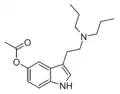

| DPT | artificial | H | CH2CH2CH3 | CH2CH2CH3 | N,N-dipropyltryptamine | 61-52-9 |